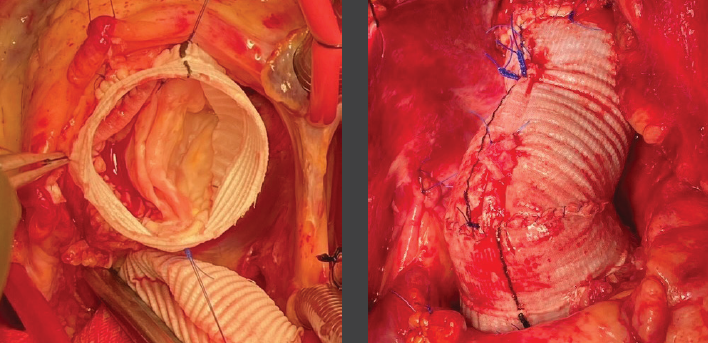

Despite a complex bicuspid aortic valve repair, the valve-sparing root replacement was a complete success; Tori recalls Dr. Bavaria’s phone call to her at the completion of the operation. “We knocked it out of the park,” he said. Now several months after the surgery, Dr. Crawford says, “It was more like a bottom-of- the-ninth walk-off grand slam!”